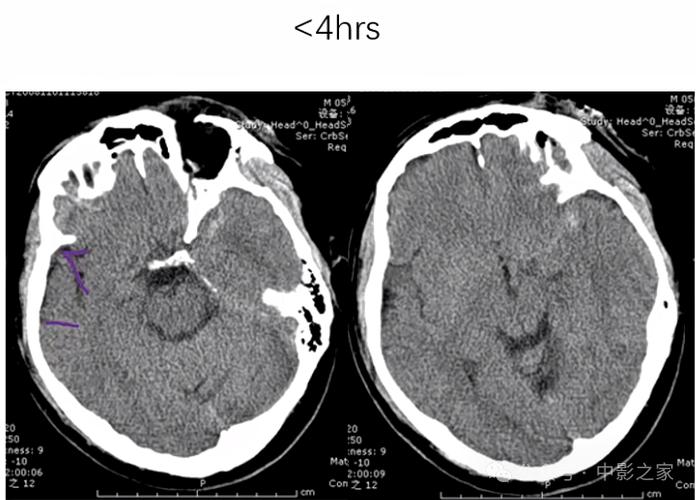

在脑梗发生的超早期(6小时内):

(图片来源网络,侵删)- 检出率很低,可能完全正常。 这是因为脑梗死的本质是脑组织缺血、缺氧,导致细胞死亡,在这个阶段,脑组织的密度还没有发生明显变化,所以CT上看不出异常,医生可能会说“CT未见明显异常”,但这绝不代表没有脑梗,尤其是在发病时间很短的情况下。